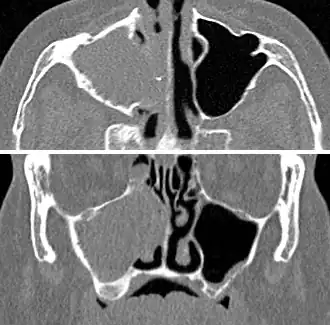

MRI image showing sinusitis. Edema and mucosal thickening appears in both maxillary sinuses.

Maxillary sinusitis caused by a dental infection associated with periorbital cellulitis

Frontal sinusitis

X-ray of left-sided maxillary sinusitis marked by an arrow. There is lack of the air transparency indicating fluid in contrast to the other side.